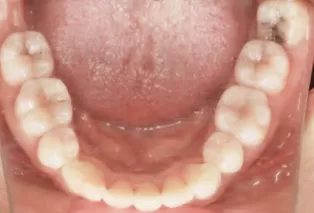

Photos intra-orales